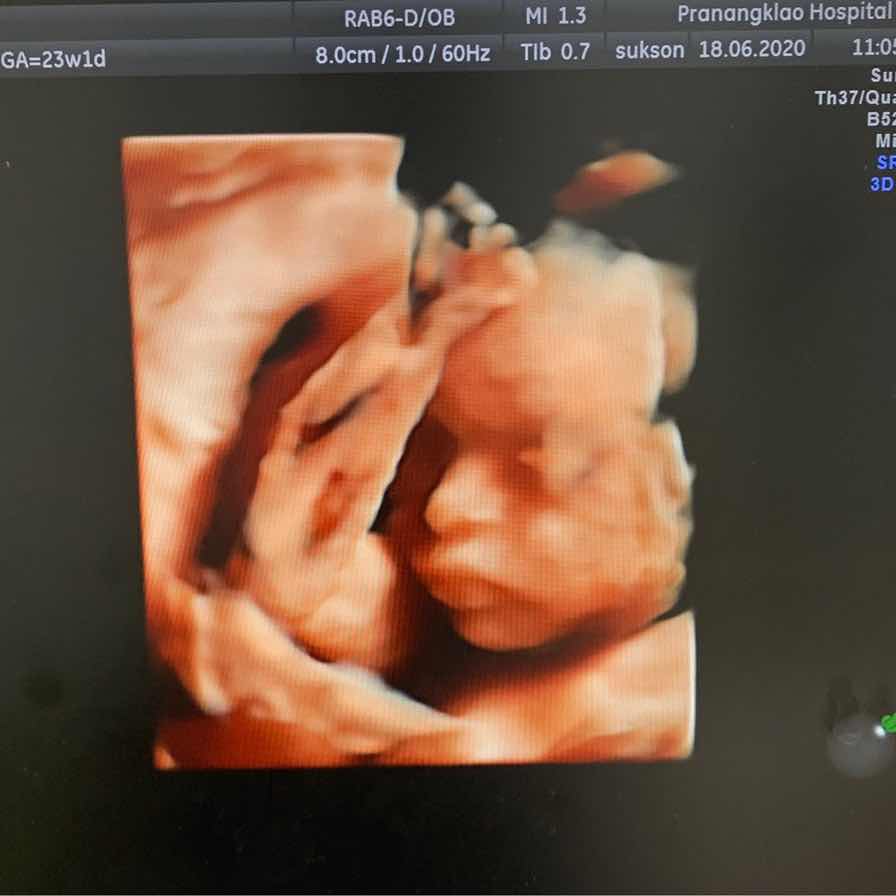

อัพเดท 25w4dค่ะ

21 week ค่ะ